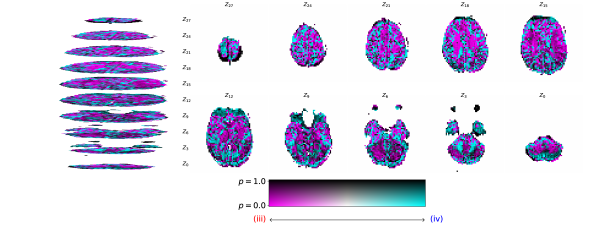

Figure 2 illustrates the distribution of residues (observed vs. estimated differences) on the fMRI volumes for the NODDI dataset. Clearly, by visual inspection, (iv) model has the darker and biggest area of shaded regions, which implies a better coverage across the brain regions and better synthesis quality. Models with topographical attention, (ii) and (iv), corresponding to Figures 2(b) and 2(d), respectively, significantly improve the synthesis, as shown by the darker and bigger areas against (i) and (iii) depicted in Figures 2(a) and 2(c), respectively. Particularly, we notice that models (i) and (iii) report difficulty in the retrieval of haemodynamical activity located in occipital and parietal lobes.

To better address which regions our baselines had more difficulty retrieving, the normalized residues were computed and are illustrated in Figure 3. Baselines – corresponding to models (i) and (ii), shown in Figures 3(a) and 3(b) respectively, which correspondingly implement a linear projection in the latent space and topographical attention –, have difficulty retrieving the prefrontal, occipital and parietal lobes, as the shade tends to a lighter grey in that region. Model (iv), shown in Figure 3(d), does not show a noticeable region with a lighter tone of grey, which implies no evident difficulty in retrieving haemodynamical activity across the different brain regions.